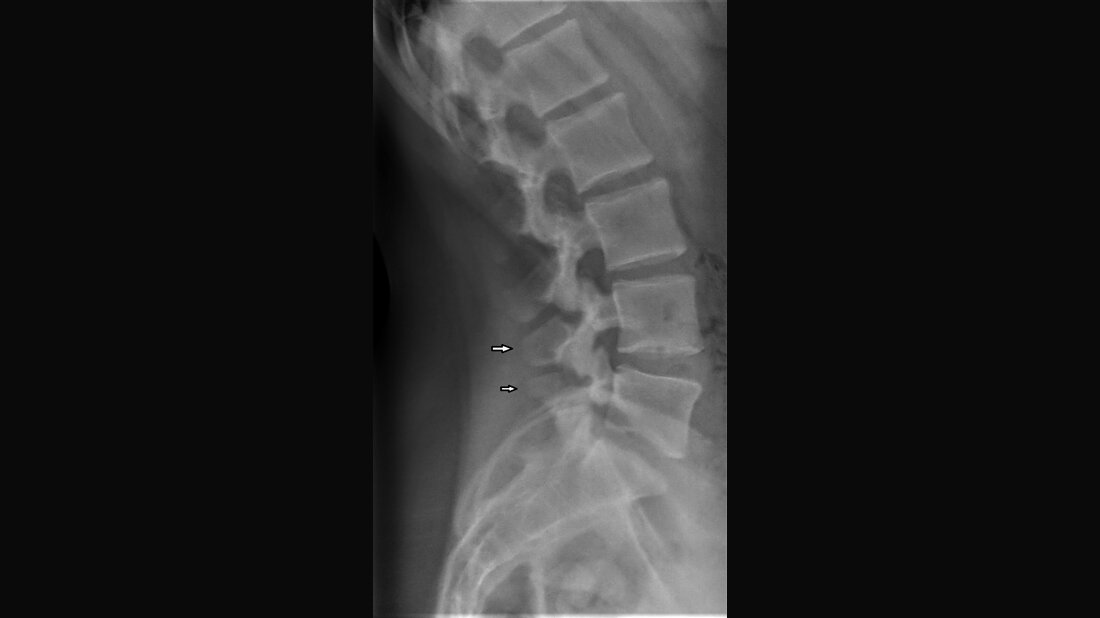

Anomalien und Normvarianten – Skelettale Veränderungen 3.35: Wirbelfortsatzdysplasien

Neben der Hypoplasie des Wirbelbogens können, nicht obligatorisch, Hypo- und Dysplasie der Wirbel- und Gelenkfortsätze, Elongation der Zwischenwirbelgelenkstücke und Spondylolysen auftreten. Die kongenitale Natur der Veränderungen ist erblich möglich.

Besides hypoplasia of the vertebral arch may occur, but not compulsory, hypoplasia and dysplasia of vertebral and articular processes, elongation of the bone situated between the joints and spondylolysis. The congenital nature of this changes is not proved, but heredity seems probable.